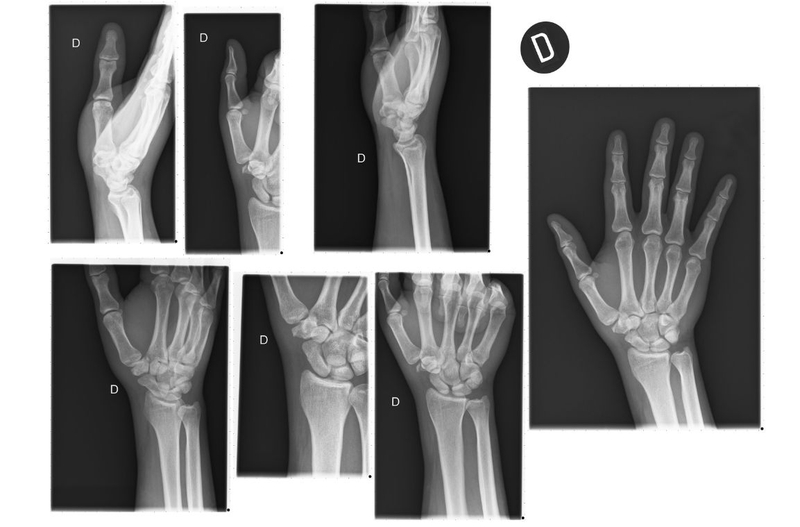

Xương cổ tay gồm nhiều xương nhỏ với hình tam giác, hình vuông, hình bầu dục khác nhau. Khi chụp X quang xương cổ tay, phim chụp sẽ thể hiện hình ảnh cấu trúc xương cẳng tay và 8 xương nhỏ. Các xương nhỏ này làm nhiệm vụ kết nối bàn tay với xương dài ở cẳng tay.

Khi chùm tia bức xạ đi qua cổ tay người bệnh, hình ảnh xương cổ tay sẽ hiển thị trên phim X quang màu trắng, các mô mềm sẽ có màu xám với sắc độ khác nhau. Sự khác nhau về màu sắc này là do khả năng hấp thụ bức xạ của các cấu trúc mô mềm hay xương là khác nhau.